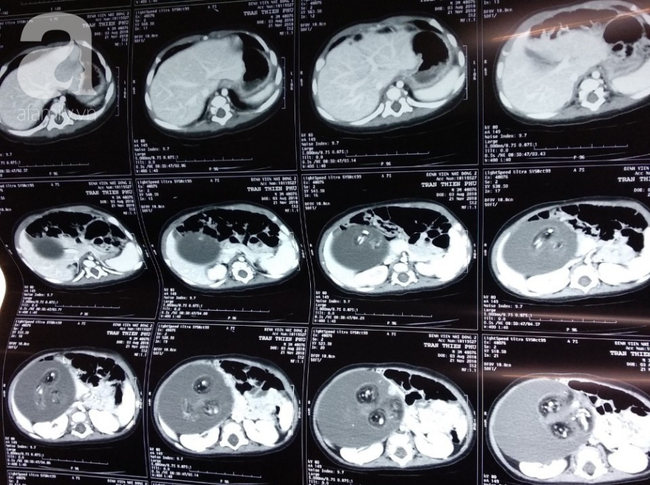

Ảnh chụp khối u trong bụng bé trai.

Ngay lập tức, bé được cho nhập viện để chụp phim CT-scan bụng qua đó phát hiện một khối gồm mô đặc, mô mỡ, mô xương kèm với hộp sọ, cột sống và xương sườn chiếm hết một nửa bụng bên phải của bé. Bệnh nhi đã được lên lịch mổ ngay sau đó.

BS Nguyễn Trần Việt Tánh, khoa Ngoại tổng hợp chia sẻ, bé trai chỉ mới 4 tháng nhưng khối u thai đã chiếm hết hơn một nửa bụng phải của bé, đường kính khoảng 12 cm và nặng 1,5 kg.

Khối u này nằm ở vị trí sau phúc mạc khá gần và dính vào các cấu trúc quan trọng, đặc biệt là bó mạch của thận phải và động mạch chậu.